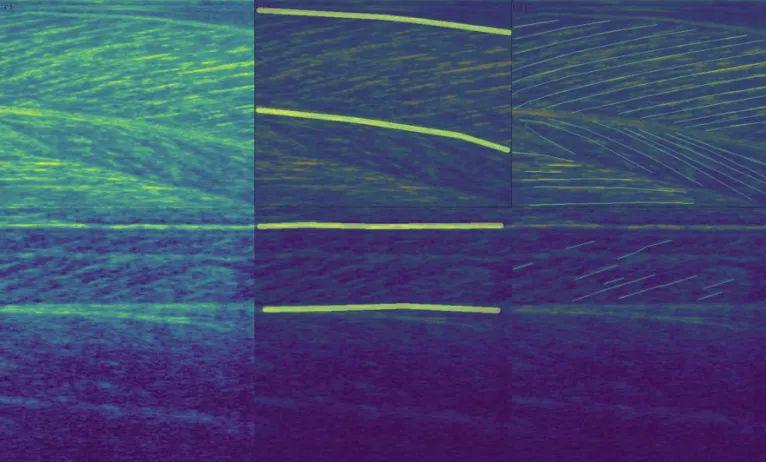

FASCICLE 小腿肌肉超声数据集

数据集链接:http://m6z.cn/631rex

FAscicle 小腿肌肉超声数据集是一个由 812 幅小腿肌肉超声图像组成的数据集,用于分析肌肉弱点并预防受伤。该数据集在文章 AW-Net:B 型超声图像上的自动肌肉结构分析以预防伤害中进行了介绍。它结合了由 Ryan Cunningham 等人发表的两篇文章“使用卷积、残差和反卷积神经网络从 B 模式超声图像中估计全区域骨骼肌纤维方向”提供的数据集。和 Neil Cronin 发表的“使用深度学习对肌肉骨骼超声图像进行自动分析”,并附有补充注释。

该 zip 文件包含两个数据集,分别分为两个由其作者命名的文件夹。每个数据集的每个图像都有一个匹配的分束分割掩码和一个可按名称识别的腱膜分割掩码。